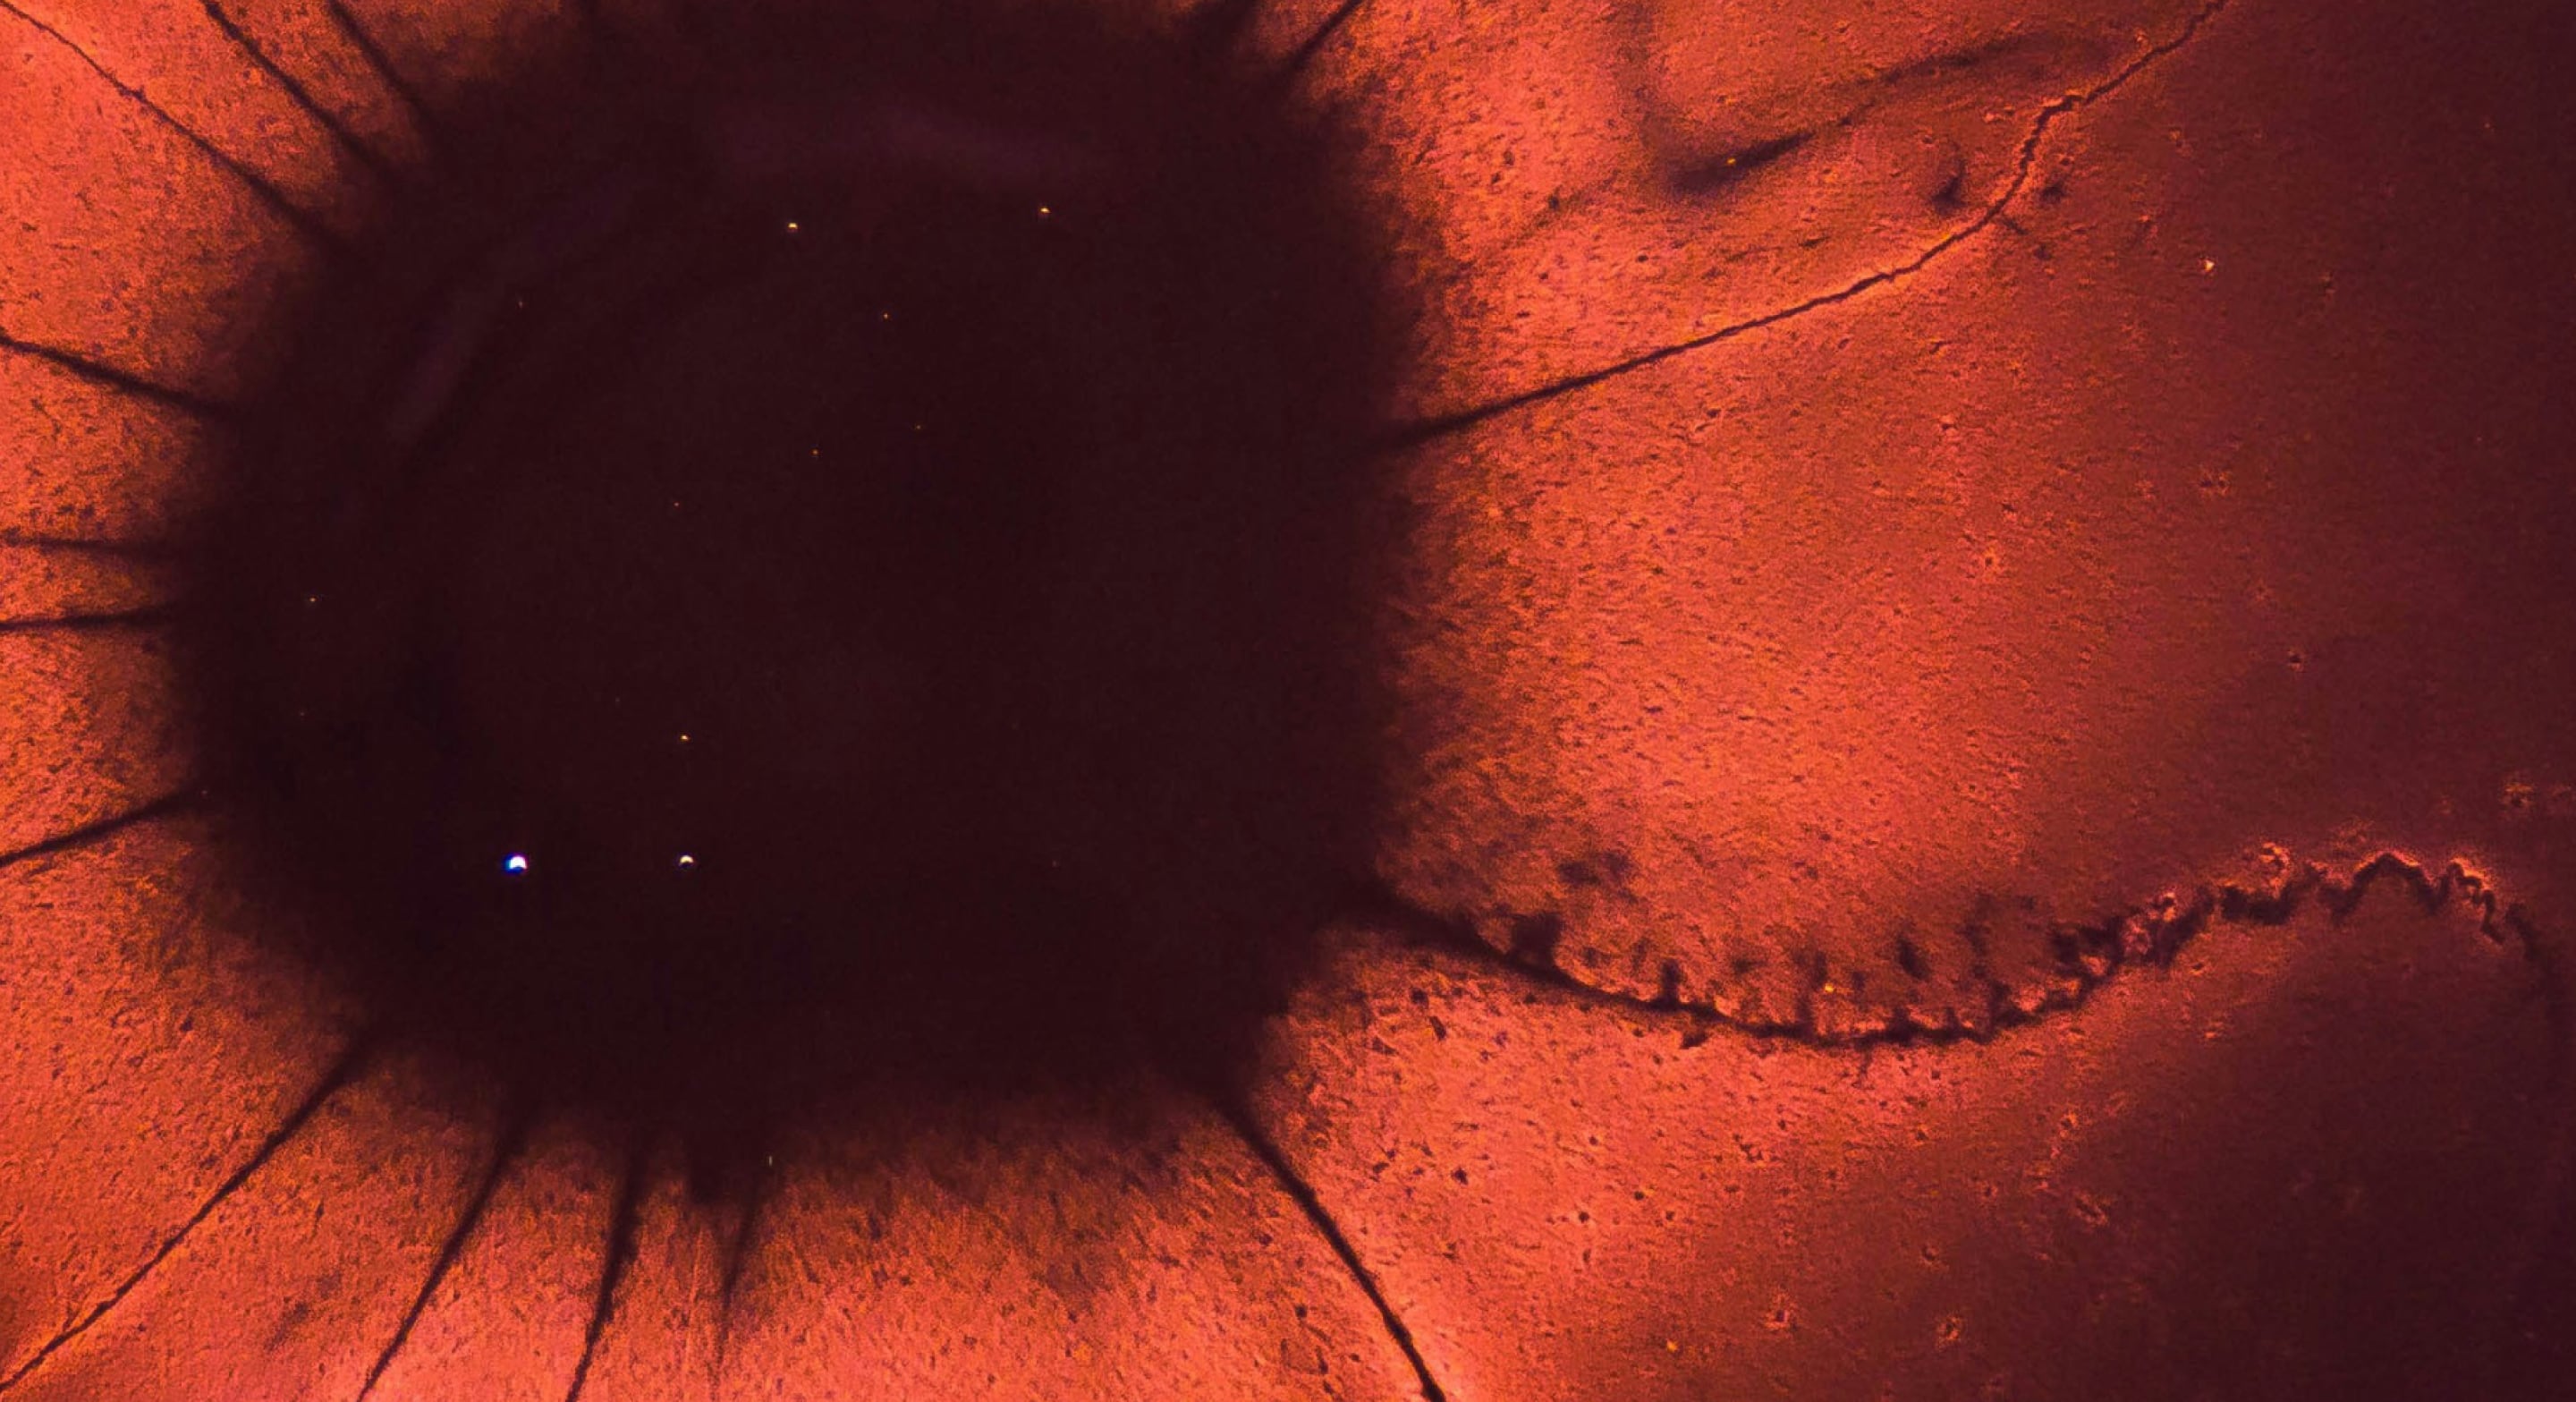

- Malaria and Neglected Tropical Diseases

- Tuberculosis and Anti-microbial Resistance